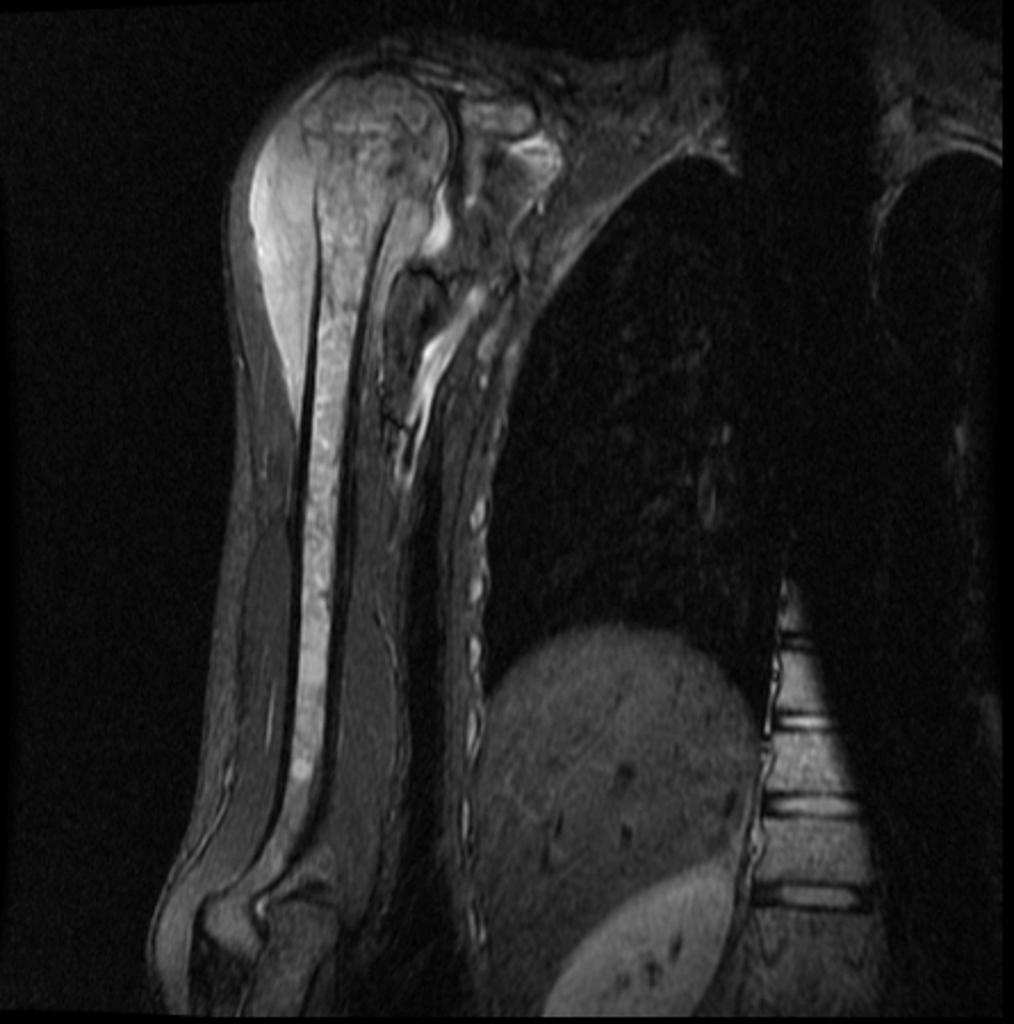

Для установления окончательного диагноза пациенту проводят компьютерную томографию или магнитно-резонансную томография костей и мягких тканей. Кроме того, выполняется ряд исследований для точной оценки характера новообразования.

Данные исследований КТ и МРТ позволят специалистам точно определить размеры новообразования, степень распространенности и поражение близлежащих тканей.

При выявлении типичных рентгенологических признаков саркомы Юинга больного направляют в отделение онкологии, где проводится расширенное обследование для оценки состояния первичного очага и выявления метастазов. В ходе такого обследования выполняется компьютерная томография или магнитно-резонансная томография костей и мягких тканей, пораженных злокачественным процессом.

Данные исследования позволяют точно определить размер новообразования, степень его распространения по костно-мозговому каналу, связь с сосудисто-нервным пучком и окружающими тканями.

Магнитно-резонансная томография (МРТ) дает дополнительную информацию относительно состояния костного мозга, мышц и соединительной ткани вокруг пораженных костей и помогает определить степень распространения опухоли.